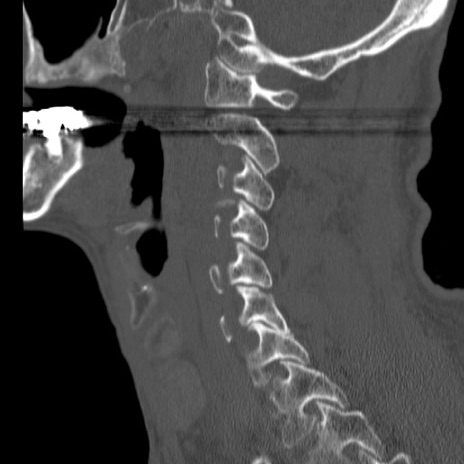

症例46 頚椎CT(矢状断像)

【症例】80歳代男性

【主訴】両側頚部〜上肢のしびれ

【現病歴】昨日、自宅内で転倒、その後より上記症状あり。意識障害なし。

【身体所見】両側上肢のallodynia(熱痛覚過敏)あり。MMTおよびDTRは正確な所見取れず。両上肢の挙上はなんとか可能。

異常所見と診断は?